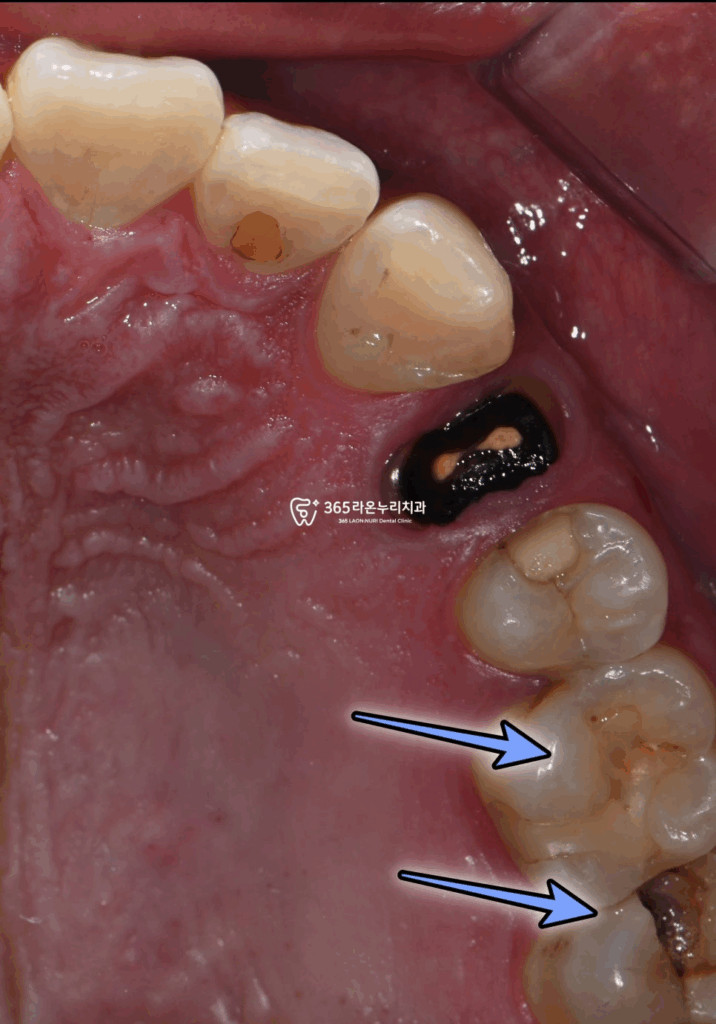

▮ 초진 및 계획

오산대역 치과 에서

초진 사진 먼저 보겠습니다.

치료기간 : 2025.4.18

표시해 둔 곳을 보면

한눈에 봐도 충치를 찾아볼 수 있는데요.